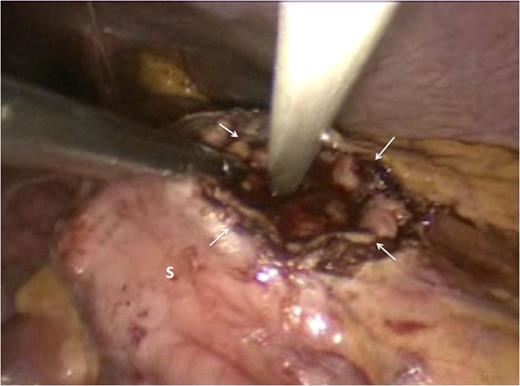

The gastric lumen was entered through the incision at the anterior stomach wall (margins indicated by white arrows). Conventional straight laparoscopic instrument can be seen developing an tunnel at the posterior stomach wall at the area where bulging from the pseudocyst is most prominent.

For this case, we used conventional 35 mm straight instruments, a rigid 30o laparoscope and no access platforms. This made the procedure technically difficult with considerable instrument ‘sword-fighting’ and limited ‘tunnel-vision’ as evident in Fig. 4. However, we used previously described techniques for SILS to complete this operation. The ‘hanging manoeuvre’ [7] was quite useful in this operation and allowed us to compensate for the absence of instrument triangulation that is inherent with the performance of SILS. We have used the ‘hanging manoeuvre’ liberally in our SILS experience [7]. It is a simple, cheap and effective manoeuvre and should be in the armamentarium of surgeons performing SILS operations.